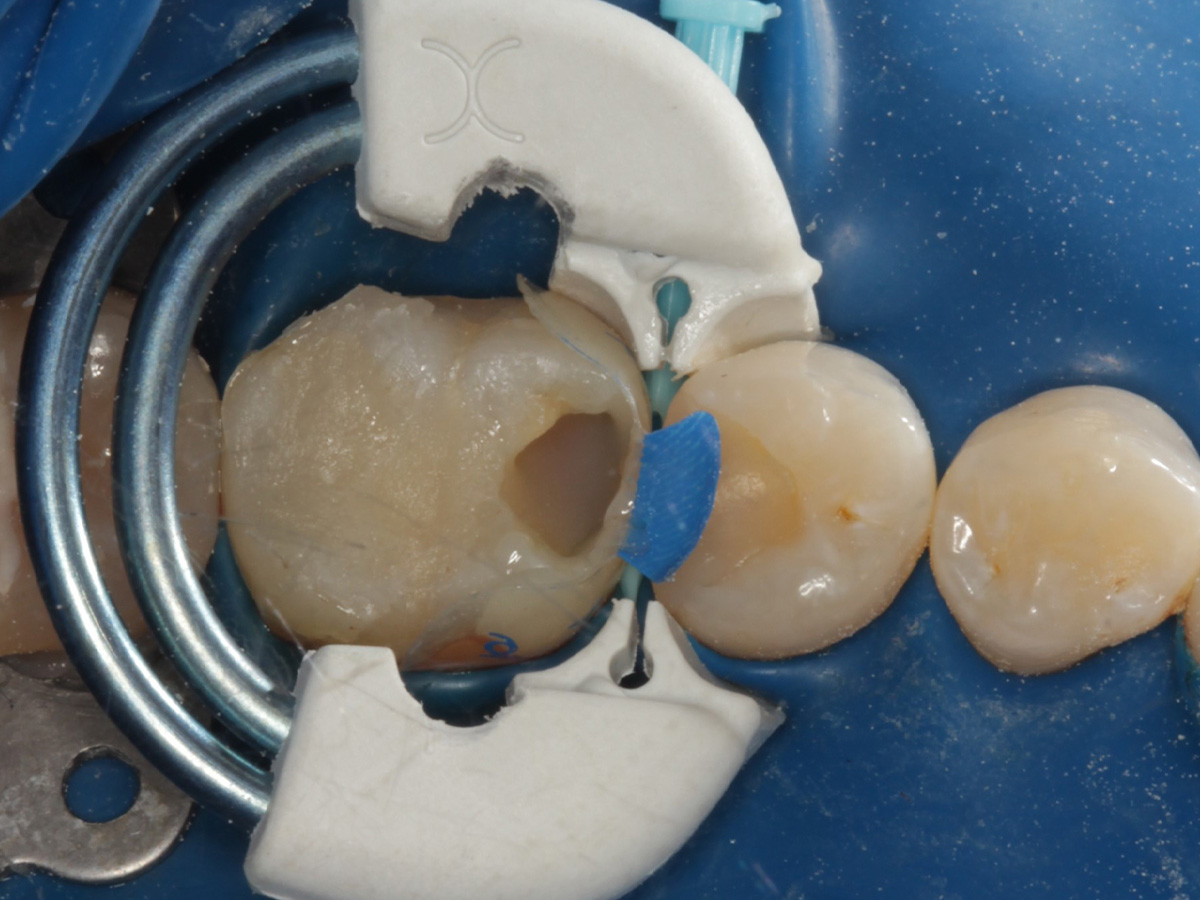

Abbildung 3

Schutz des Nachbarzahnes und des Kofferdams mit wiederverwandter Bioclear Biofit Matrize (gereinigt und sterilisiert); Separation zur Applikation der Matrize mit Heidemannspatel

Abbildung 4

Defektdarstellung; „Schutzmatrizen“ ideal als „Leitplanken“ bei der Zahnpräparation tief approximal bis in gesunde Zahnsubstanz